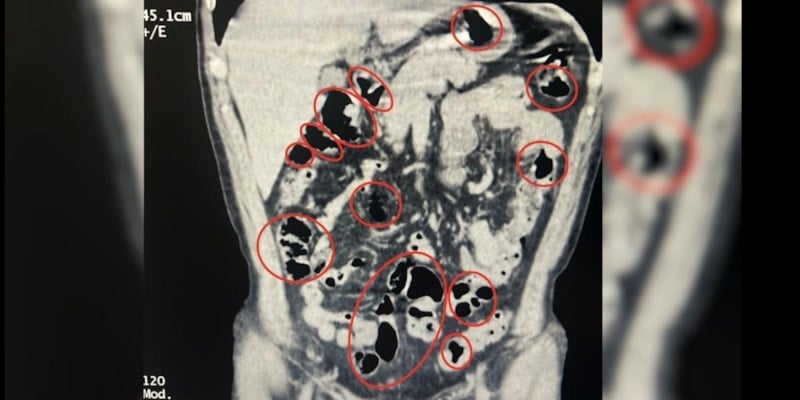

Tatvan Devlet Hastanesi'ne götürülen şüphelilerin burada yapılan röntgen ve tomografi incelemelerinde de mide ve bağırsaklarında yabancı cisimler tespit edildi.

Tıbbi müdahale sonucu şüphelilerin yuttuğu 14 kapsül çıkarıldı.